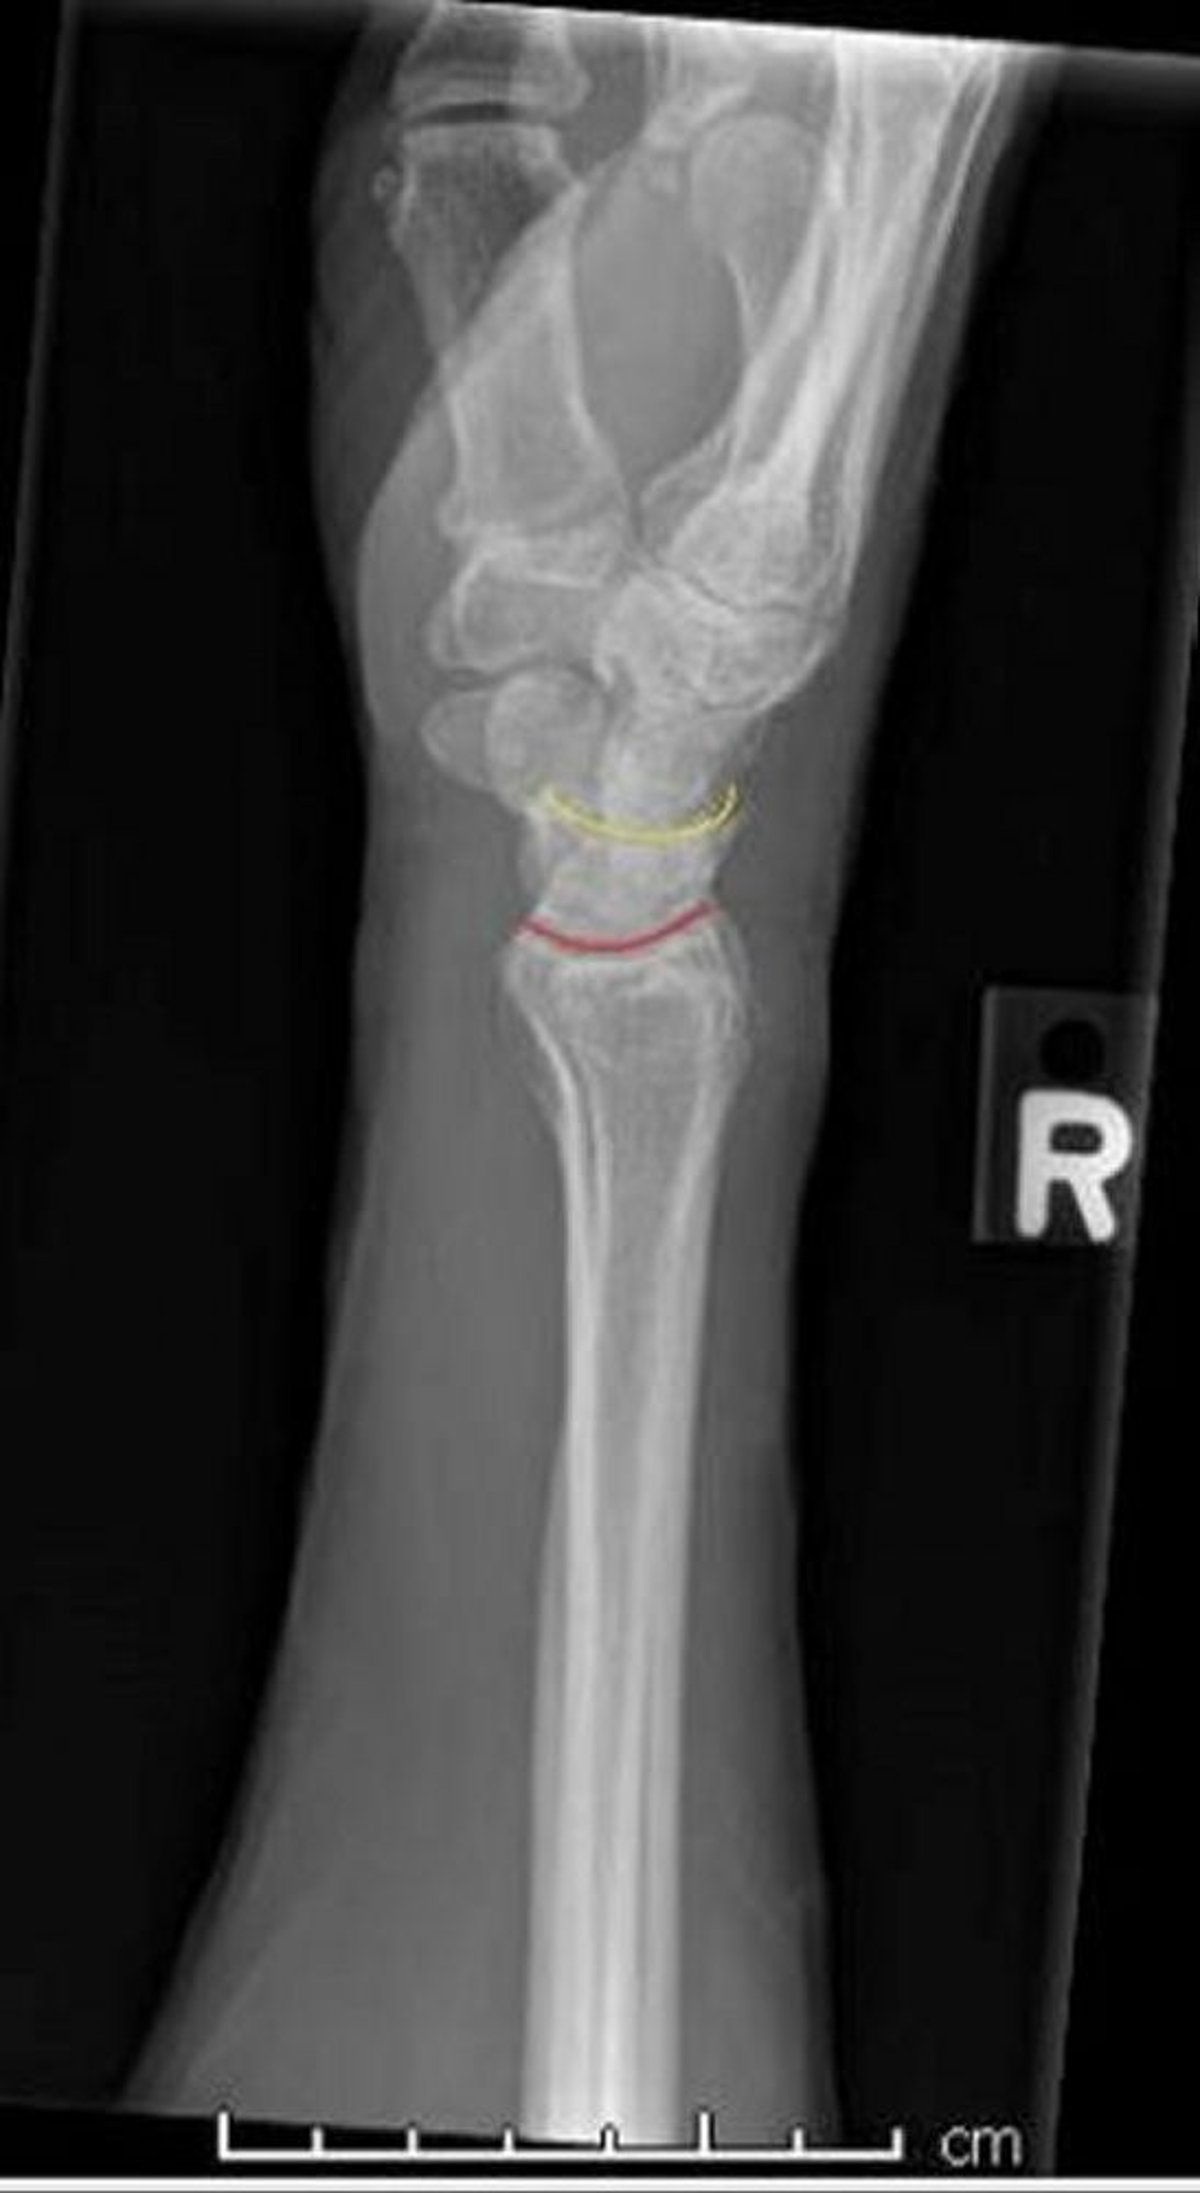

Muñeca normal: proyección lateral

Esta proyección lateral de una muñeca normal muestra la superficie de contacto normal entre el radio y el semilunar (línea roja), y entre el semilunar y el hueso grande (línea amarilla).

Image courtesy of Danielle Campagne, MD.